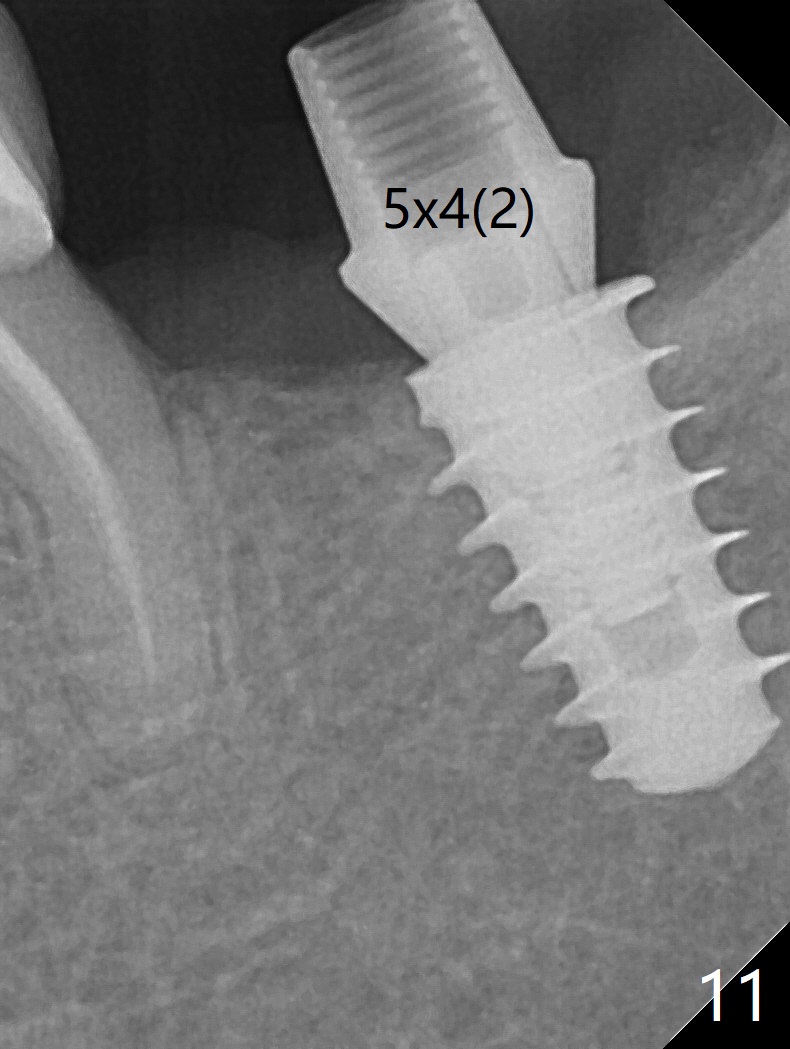

In fact, the mesial crest of the socket could be used as a more secure landmark (bony vs. soft tissue) for osteotomy depth (Fig.4 arrowhead) with drill stopper. To place the implant subcrestal, the initial osteotomy should be 1-2 mm deeper. When she returns 2 years 9 months postop, the wound has healed. The implant needs to be uncovered. Make sure to have clearance for a healing abutment. Use sensor 1 for PAs before and after uncover. The implant appears to be tilted distal. An angled abutment may be required. Take PA for seating confirmation. Guided surgery is preferable. The implant plateau is covered by the bone 2 years 9 months postop (Fig.8 *). The healing screw is removed with difficulty, while a 6x3 mm healing abutment is placed with resistance, probably related to interference from the distal crest (Fig.9 *). It is much easier with removal of the crest bone using surgical bur, because of clearance (Fig.10 *). It is the best to have a particular drill to remove the excess bone. There is no interference to insert and torque a 5x4(2) mm pair abutment 2 weeks post uncover (Fig.11). Due to poor trajectory (guide necessity) and tight proximal contact, the crown is not completely seated (Fig.12). However, the abutment screw is unlikely to get loose in the future.